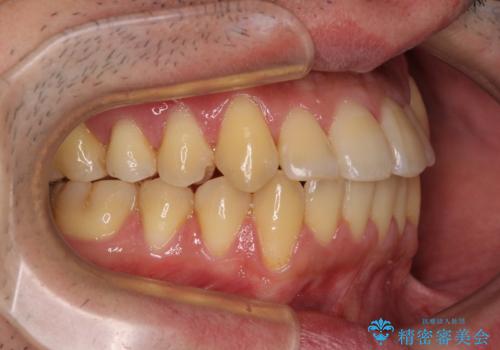

八重歯とクロスバイト 目立たないワイヤー装置で矯正治療

- 八重歯と前歯のクロスバイトを改善したいとのことで来院された患者様です。

マウスピース矯正での自己管理には自信がないとのことで、ワイヤー装置による矯正治療を行うこととしました。

デコボコの程度は強かったのですが、口元の突出感はなかったため、非抜歯矯正としました。